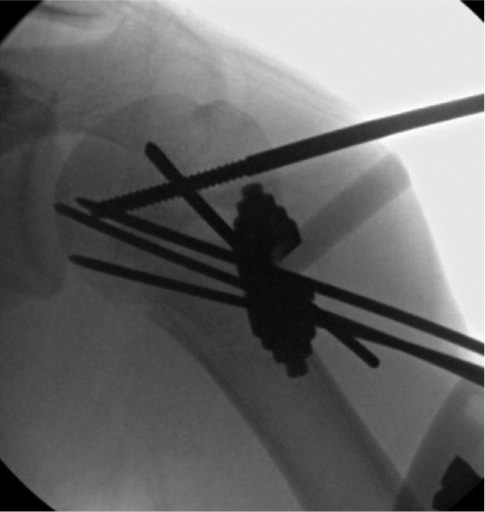

Once the fracture is reduced and stabilized, the arm is rotated under fluoroscopic imaging to ensure fracture stability and that the pins are confirmed to be within the humeral head and not intra-articular. Pins are cut and plastic balls are clamped to pin ends, or the pins are bent over the skin and cut off with sterile felt pads between the plastic ball/pins and the skin. We choose to immobilize in a coaptation splint that extends up over the deltoid for 3-4 weeks, which helps avoid pin migration. We leave this splint on until pins are then pulled in clinic with sling/swath immobilization for another 2-3 weeks. Some practitioners have found that some of these pins can migrate out over time and will then clamp some of the pins together with small external fixation components (Figure 11). Swarup et al. detail placing the patient in either a supine or beach chair position and using closed reduction techniques similar to those outlined above.11 If closed reduction fails, then open reduction via a deltopectoral approach is used. The fracture is secured with two 2.5 mm threaded pins left outside of the skin and further stabilized with a pin-to-pin clamp. Pins are left in place for approximately 4 weeks and removed in the office or under sedation.

Figure 11. After reduction and pin fixation, a small external pin to bar fixator construct can be used to prevent pin migration.

jposna2023703_fig11.jpg